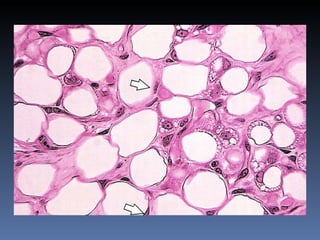

TECIDO ADIPOSO Duas variedades de tecido adiposo: Tecido adiposo amarelo (unilocular) Tecido adiposo pardo,  multilocular

Tecido Adiposo Unilocular

Tecido Adiposo Multilocular

TECIDO ADIPOSO Tecido adiposo amarelo ou unilocular Cor devida a presença de carotenos dissolvidos nas gotículas de gordura Praticamente todo o tec, adiposo em adultos é do tipo unilocular Acúmulo do tc. Adiposo unilocular em certas regiões é influenciado pelo sexo e idade

TECIDO ADIPOSO Tecido adiposo amarelo ou unilocular Forma o panículo adiposo (camada sob a pele), de espessura uniforme Deposição seletiva com a idade é regulada por hormonios esteroides (adrenal) Células adiposas grandes 50 – 150 micrometros Demonstração dos lipídeos por corantes específicos em cortes congelados

TECIDO ADIPOSO Duasvariedades de tecido adiposo: Tecido adiposo amarelo (unilocular) Tecido adiposo pardo, multilocular

TECIDO ADIPOSO Tecidoadiposo amarelo ou unilocular Cor devida a presença de carotenos dissolvidos nas gotículas de gordura Praticamente todo o tec, adiposo em adultos é do tipo unilocular Acúmulo do tc. Adiposo unilocular em certas regiões é influenciado pelo sexo e idade

TECIDO ADIPOSO Tecidoadiposo amarelo ou unilocular Forma o panículo adiposo (camada sob a pele), de espessura uniforme Deposição seletiva com a idade é regulada por hormonios esteroides (adrenal) Células adiposas grandes 50 – 150 micrometros Demonstração dos lipídeos por corantes específicos em cortes congelados